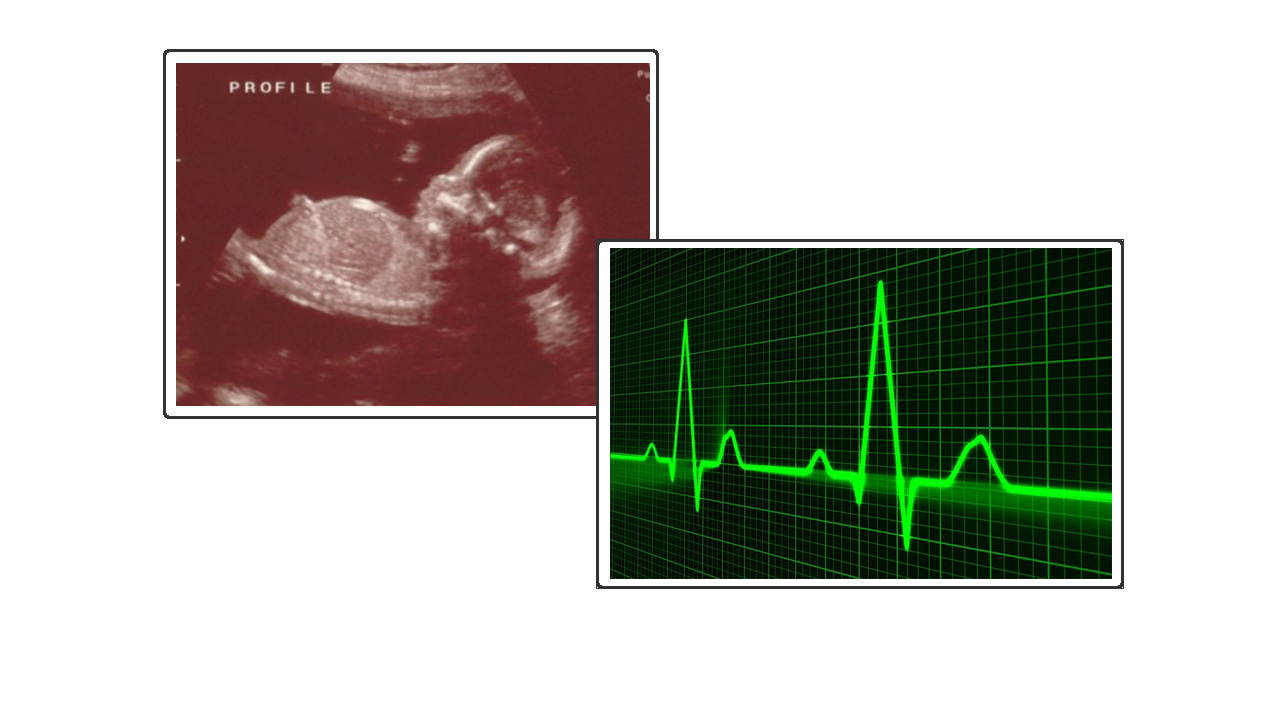

Then two weeks later we took our growing baby for a cardiac scan. They also told us at 17 weeks he had a partial AVSD (Atrioventricular Septal Defect), but that didn’t seem to matter down's syndrome kept playing in my mind. The hospital service were fantastic: they gave clear information in words we could understand and also reassured us this was so common in babies like our son that it could be fixed!

Cardiac scan at 17 weeks identifies AVSD

(Atrioventricular Septal Defect)